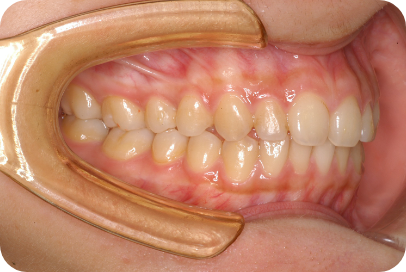

Tさん

Before

After

- 形態:狭いV型の上顎を丸くて広いU型に改善、歯ならび、咬み合わせの改善

- 機能:咀嚼嚥下トレーニング、口腔周囲筋トレーニング、姿勢改善